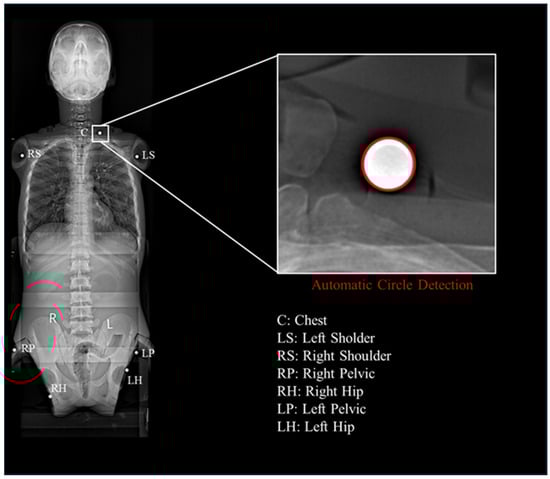

2.2. Fix Markers

2.5. Fitting the Centers of Steel Beads